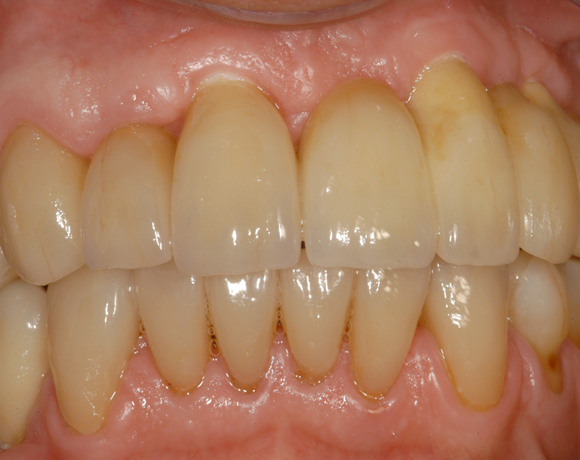

6 Implantate und viele Kronen und Brücken

Mit dem zweiteiligen vollkeramischen Implantat lassen sich auch große Lücken überbrücken.

Ein Projekt aus dem Jahr 2011

Im vorliegenden Patientenfall waren die Zähne 11 – 26 mit einer provisorischen Brücke versorgt, der Patient konnte damit aber nicht essen. Auch im Unterkiefer waren die vorhandenen Kronen und Brücken insuffizient. Es wurde eine komplette Neuversorgung für Ober- wie Unterkiefer geplant.